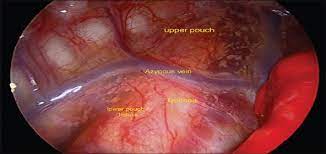

قیمت: 25٬000 تومان - دسته بندی فایل: پاورپوینتپاورپوینت آترزی مری و فیستول تراکئو ازوفاژ (ppt) 11 اسلاید

فروش ویژه پاورپوینت حرفه ای آترزی مری وفیستول تراکئو ازوفاژ / تعداد اسلاید: 11 اسلاید